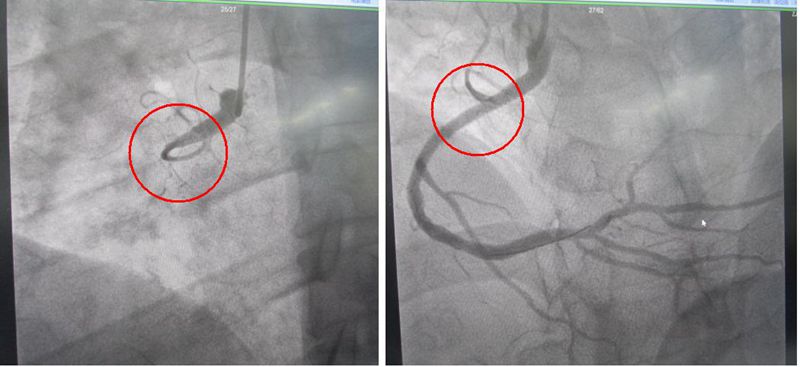

冠脉造影500例,其中急诊冠脉造影60例。开机两个月,独立开展急诊PCI术,为急性心梗病人行急诊PCI术治疗50例,6名患者发生室颤,不少患者发生了室速、停搏、低血压、休克等严重临床状况,全部抢救成功。